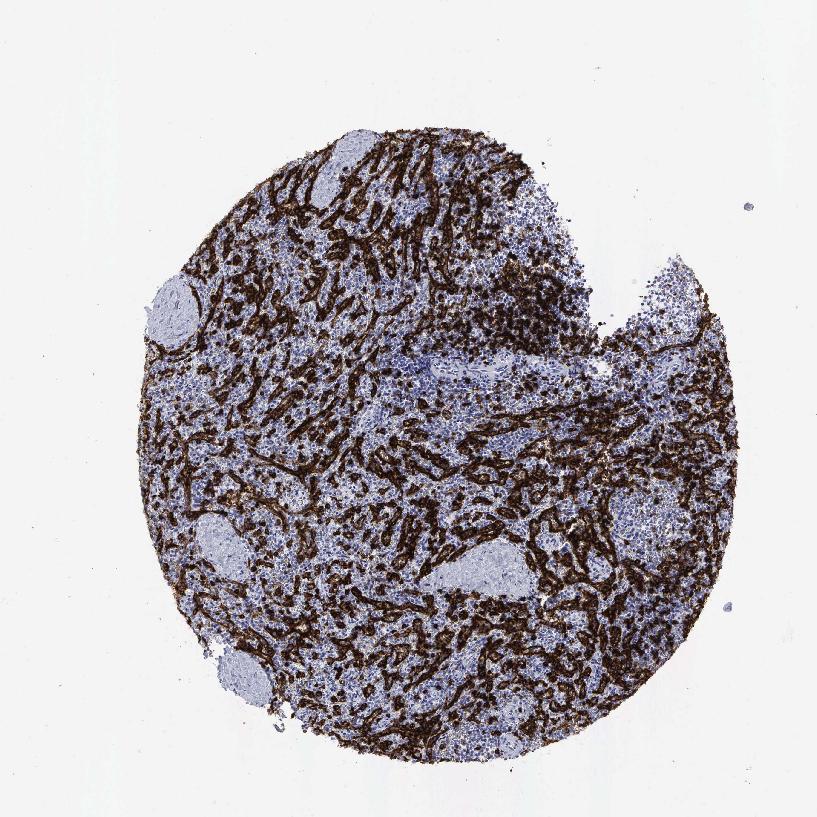

TISSUE PRIMARY DATA SPLEEN Show tissue menu

Spleen

SPLEEN - Expression summary

Protein expression

Cells in red pulp: High

Cells in white pulp: High

SPLEEN - Antibody stainingi

Antibody staining in the annotated cell types in the current human tissue is reported as not detected, low, medium, or high, based on conventional immunohistochemistry profiling in selected tissues. This score is based on the combination of the staining intensity and fraction of stained cells.

Each image is clickable and will lead to virtual microscopy that enables deeper exploration of all samples and also displays staining intensity scores, fraction scores and subcellular localization as well as patient and tissue information for each sample.

Antibody HPA037756Antibody CAB000012Antibody CAB075722

Cells in red pulp MediumHighMedium

Cells in white pulp MediumHighMedium